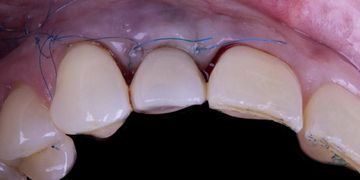

- Bundle and alveolar bone;- The role of keratinized tissue versus soft tissue thickness;- Mucogingival surgery for soft tissue dehiscence coverage around implants;- Mucogingival approach in combination with immediate post extraction implant placement and immediate loading;- Soft tissue augmentation and simultaneous guided implant placement in the aesthetic zone;- The soft tissue approach for implant installation after tooth extaction for periodontal reason;- Soft tissue augmentation procedures in edentulous areas before implant rehabilitation;- Step by step protocol of the split-full-split elevation technique to obtain coronal advancement of the flap;- Step by step protocol of connective tissue graft harvesting technique;- Step by step protocol of the “connective tissue platform technique” for soft tissue augmentation.